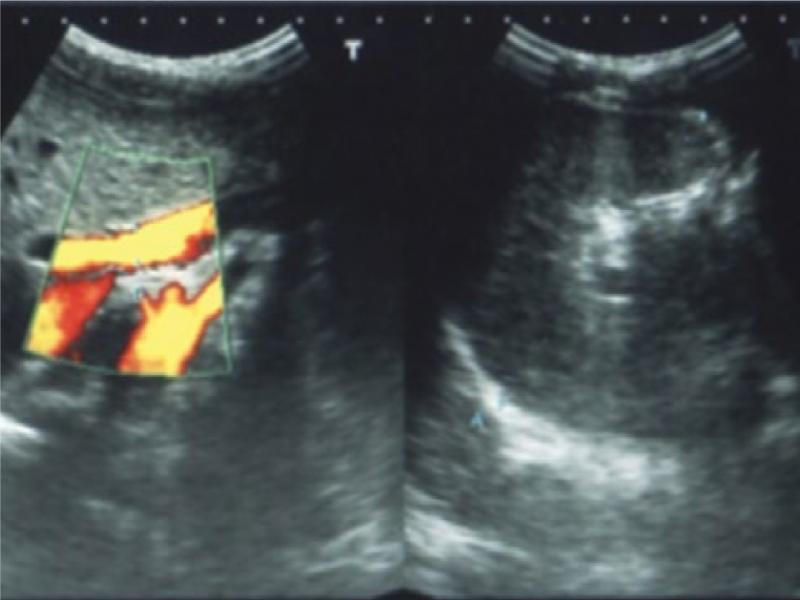

Fig. 3.